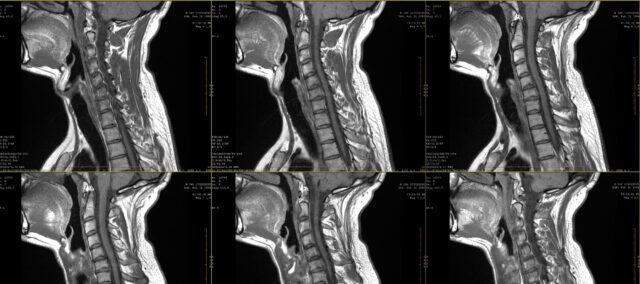

S cieľom preskúmať zhodu medzi kresbami radikulárnej bolesti a nálezmi na MRI boli do tejto štúdie zaradení účastníci s 2-mesačnou anamnézou pretrvávajúcej bolesti, u ktorých bola na MRI diagnostikovaná cervikálna radikulopatia. Túto diagnózu stanovil neurochirurg na základe klinických informácií a nálezov MRI, ktoré hodnotil rádiológ.